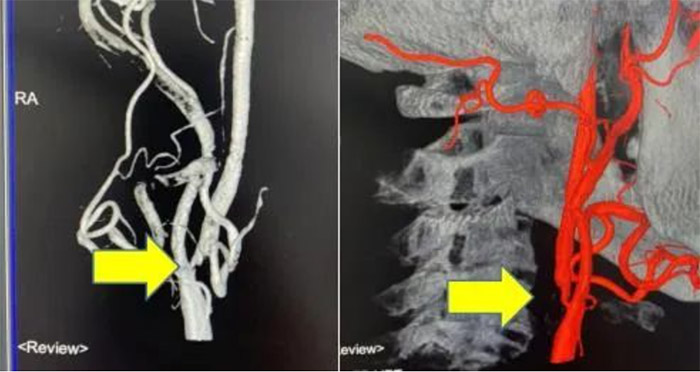

术后复查CTA可见血管狭窄解除